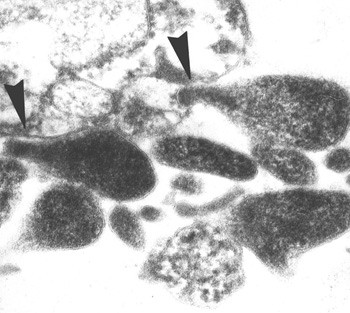

M genitalium ble isolert første gang i 1980, fra to av 13 menn med ikke-gonoreisk uretritt (2). Bakterien er svært vanskelig å isolere ved dyrking, og på verdensbasis er kun et fåtall stammer dyrket frem (fig 1). Mikrobene i familien Mycoplasmataceae er primitive bakterier med få gener involvert i biosyntetiske prosesser. M genitalium mangler alle gener involvert i aminosyresyntese, hvilket gjør den helt avhengig av eksogen tilførsel av det komplette spekter av aminosyrer. Dette kan forklare hvorfor bakterien er så vanskelig å dyrke. Mangelen på egen aminosyresyntese gjør at M genitalium, i likhet med C trachomatis, er en intracellulær bakterie. M genitalium er en av de minste frittlevende bakteriene som finnes. Sammen med de øvrige mykoplasmene skiller den seg fra andre bakterier ved mangelen på cellevegg (3). Dette gjør den upåvirkelig av penicilliner og kefalosporiner.

Det å påvise en sammenheng mellom M genitalium og infeksjon i øvre genitaltractus med eventuelle senfølger, som infertilitet og kroniske bekkensmerter, er avgjørende for at infeksjonen skal bli oppfattet som alvorlig. På dette området er det et behov for ytterligere forskning. Imidlertid peker flere studier i retning av at infeksjon med M genitalium er mer enn en ufarlig «snue» i genitalorganene. Mikroben fører til egglederbetennelse etter innpodning på aper (23, 24). Det er vist at M genitalium adhererer til humant egglederepitel i organkulturer (25). Mikroben er også funnet i forbindelse med akutt endometritt (26) (fig 2). I en pasient-kontroll-studie ble infeksjon med M genitalium i endocervix påvist hos 13 % og C trachomatis hos 27 % av 45 kvinner med klinisk diagnostisert bekkeninfeksjon, mens bakterien ikke ble påvist hos noen av de 37 kontrollpersonene. Bare én pasient hadde koinfeksjon med C trachomatis, hvilket støtter teorien om at M genitalium alene kan forårsake øvre genitalinfeksjon/bekkeninfeksjon (27). I en nyere studie har man påvist M genitalium i egglederen hos en kvinne med laparoskopisk diagnostisert akutt salpingitt (28).